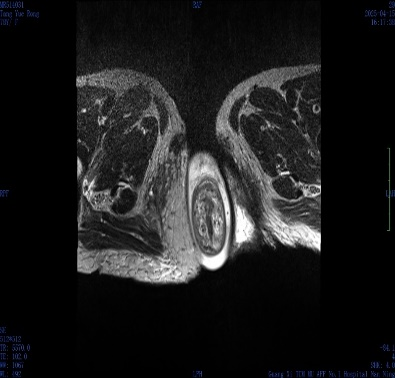

肛肠外科检查发现,周奶奶的肛门处有约 8 cm 脱出肿物,呈「宝塔状」,肛门括约肌明显松弛。结合排粪造影及 MRI 提示,诊断为 III 度直肠脱垂。